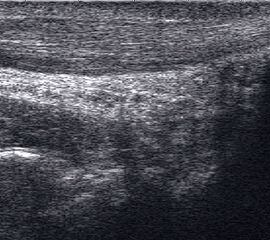

Tendopathien der Flexorensehnen

Dorsaler TS hinter dem Innenknöchel.

Abbildung 46

Lagerung: Rückenlage, Außendrehung des Beines.

Schnittführung: TS und LS hinter dem Innenknöchel beginnen und bis zum Os cuneiforme mediale fortführen.

Referenzstrukturen: Innenknöchel, Talus, Os naviculare, Os cuneiforme mediale, Sehnen der Mm tibialis posterior, flexor hallucis longus, flexor digitorum.

Befunde: Häufig betreffen die Pathologen die Tibialis-posterior-Sehne, die als erste Sehne hinter dem Innenknöchel zur Darstellung kommt. Halo-Phänomen und echoarme Verdickung bei akuter Tendinopathie, zunehmend inhomogen und echogen mit Kaliberschwankungen bis hin zu Teilrupturen bei Chronifizierung 5. Für die Erkennung von Teilrupturen sind TS in verschiedener Höhe besonders wichtig. Bei komplettem Riss mit Retraktion im LS Bild wie Spargelspitze mit umgebender Flüssigkeit oder Hämatom. Ein Os tibiale externum erscheint als echoreiche Struktur im Verlauf der Tibialis posterior Sehne mit dorsaler Schallauslöschung. Ein Os naviculare cornutum imponiert als starke Prominenz im Ansatzbereich der Tibialis posterior Sehne.